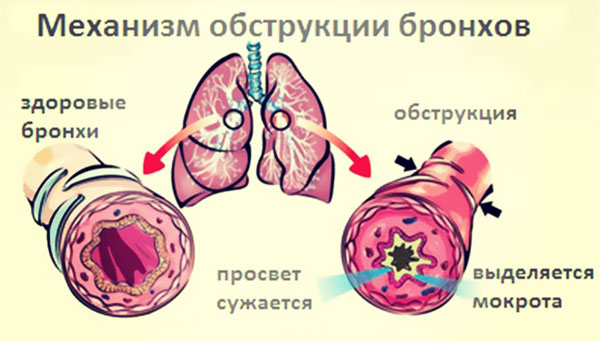

Обструктивний бронхіт – це спазм бронхів, при якому слиз не може вийти назовні і накопичується в бронхах людини.

- Відновлення прохідності бронхів – лікування обструкції з використанням симпатоміметиків у вигляді сиропів або інгаляцій;